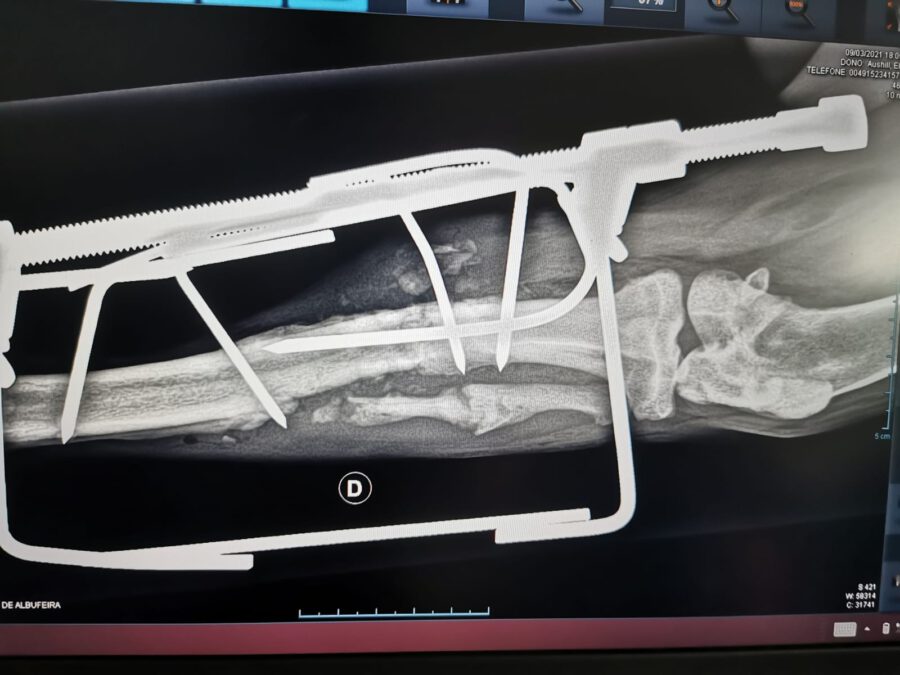

And again we received a call for help from a dedicated animal welfare activist who had found an injured young dog in a gipsy camp and asked us for help. The little guy had a broken leg. Since then he was forced to hobble around with the broken leg. Our helpers went to collect him and took him to the vet. An x-ray revealed that the leg is definitely broken and needed surgery. Fortunately, his blood tests showed that he does not suffer from heart worms, tick bite fever nor Leishmaniasis. On 11/03/2021 his leg was operated on. Now his is in foster care with Elena, where he can recover.